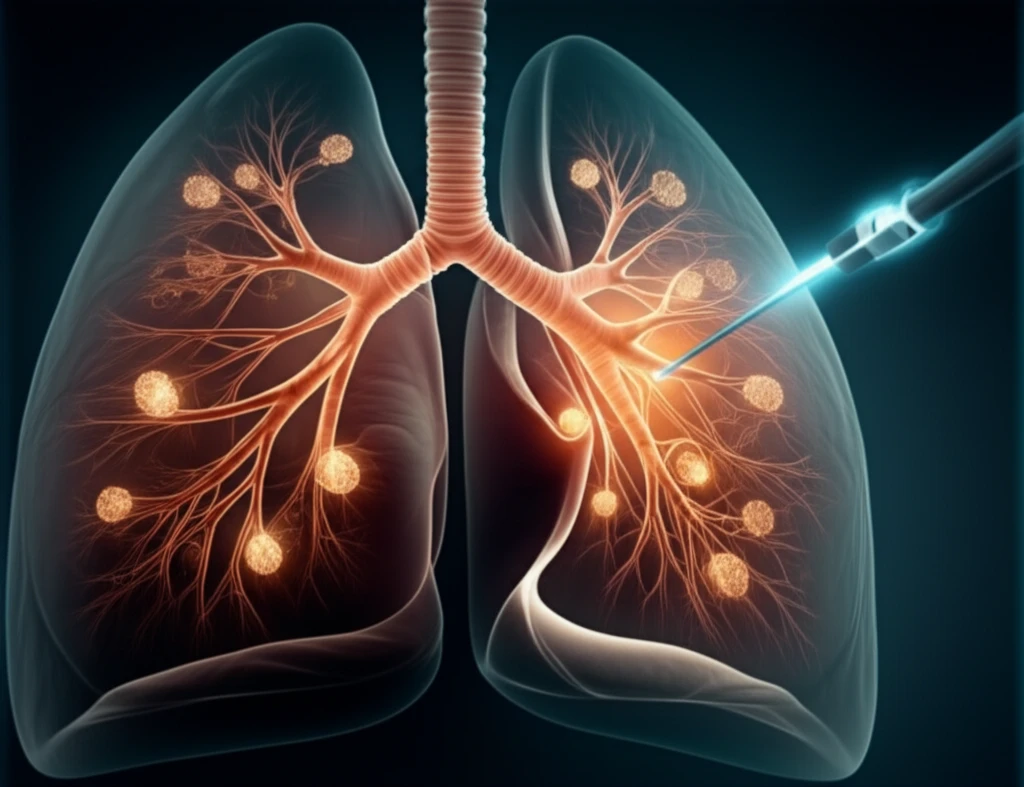

The surgical removal of lung metastases is a topic of considerable debate within oncological and thoracic surgery circles. A central question persists: Does surgical resection truly enhance survival rates, or is the observed success simply a result of patient selection? Currently, concrete randomized evidence is lacking as we await the results from ongoing clinical trials.

Unlike bronchogenic carcinoma, lung metastases are blood borne, and various surgical techniques have been refined to preserve lung tissue during removal. These methods range from clamping and suturing to laser ablation. Yet, establishing a definitive safe margin around these lesions remains an ongoing challenge.

A recent study involving 335 patients who underwent 679 wedge resections for colorectal lung metastases revealed a 20.6% five-year risk of local recurrence. The research identified two significant factors: increasing the margin length decreased recurrence risk, whereas larger tumor size increased it. A margin length at least half the tumor size was deemed safe, reducing local recurrence to below 11%.

Pulmonary metastatic disease will continue to be a focal point of research. The present study offers a timely contribution, indicating that maintaining a margin length of at least half the tumor size can indeed minimize the risk of recurrence. Further investigation and collaborative efforts are essential to refine treatment strategies and improve outcomes for patients with lung metastases.